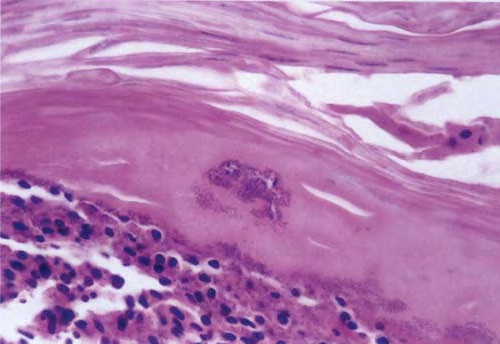

The initial lesion is a transient vesicle or pustule  that quickly evolves into a honey-colored crusted plaque that can enlarge to greater than 2 cm in diameter . Surrounding erythema may be present. Constitutional symptoms are absent. Regional lymphadenopathy may be present in up to 90 percent of patients with prolonged, untreated infection. Untreated, the lesions may slowly enlarge and involve new sites over several weeks. In some individuals, lesions resolve spontaneously. In others, the lesions extend into the dermis, forming an ulcer (see Staphylococcal Ecthyma